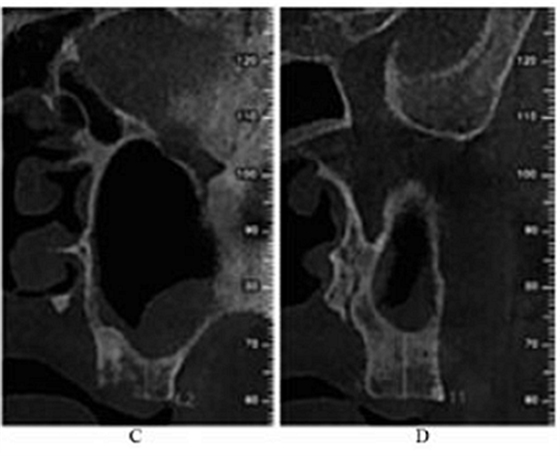

治疗过程:左侧上颌局麻下,于25~28牙区作梯形切口,翻瓣。用直径6mm的去骨环钻于25牙远中根尖处开窗,去除游离骨片,见窦膜完整,剥离窦膜。从开窗处穿刺抽出约2mL淡黄色粘稠液体,生理盐水加庆大霉素冲洗窦腔至冲洗液清亮,窦膜穿孔处放1.5 cm×2.5 cm胶原膜1片,在窦底与胶原膜之间植入骨粉1g,开窗表面覆盖2 cm×2.5 cm胶原膜1片及富血小板纤维蛋白膜3片,减张缝合(图2)。

图2 上颌窦外提升术中。注:A,开窗;B,抽出液体;C,植入骨粉;D,缝合。